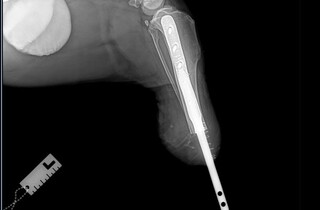

У Харкові вперше поставили біоінтегрований протез собаці, якого скалічили росіяни. Допоміг тварині хірург-ветеринар Віталій Клубань та його колеги. Він повідомив у Facebook про здійснення вдалої операції на базі Салтівської ветеринарної клініки.

56-кілограмовий чорний тер'єр потрапив під касетний обстріл росіян біля дитячого садочка в Харківській області та втратив лапу.

Лікарі провели собаці надскладну операцію та вживили біоінтегрований протез.

Наразі тер'єр вже встиг звикнути до «нової» кінцівки та вправно бігає.